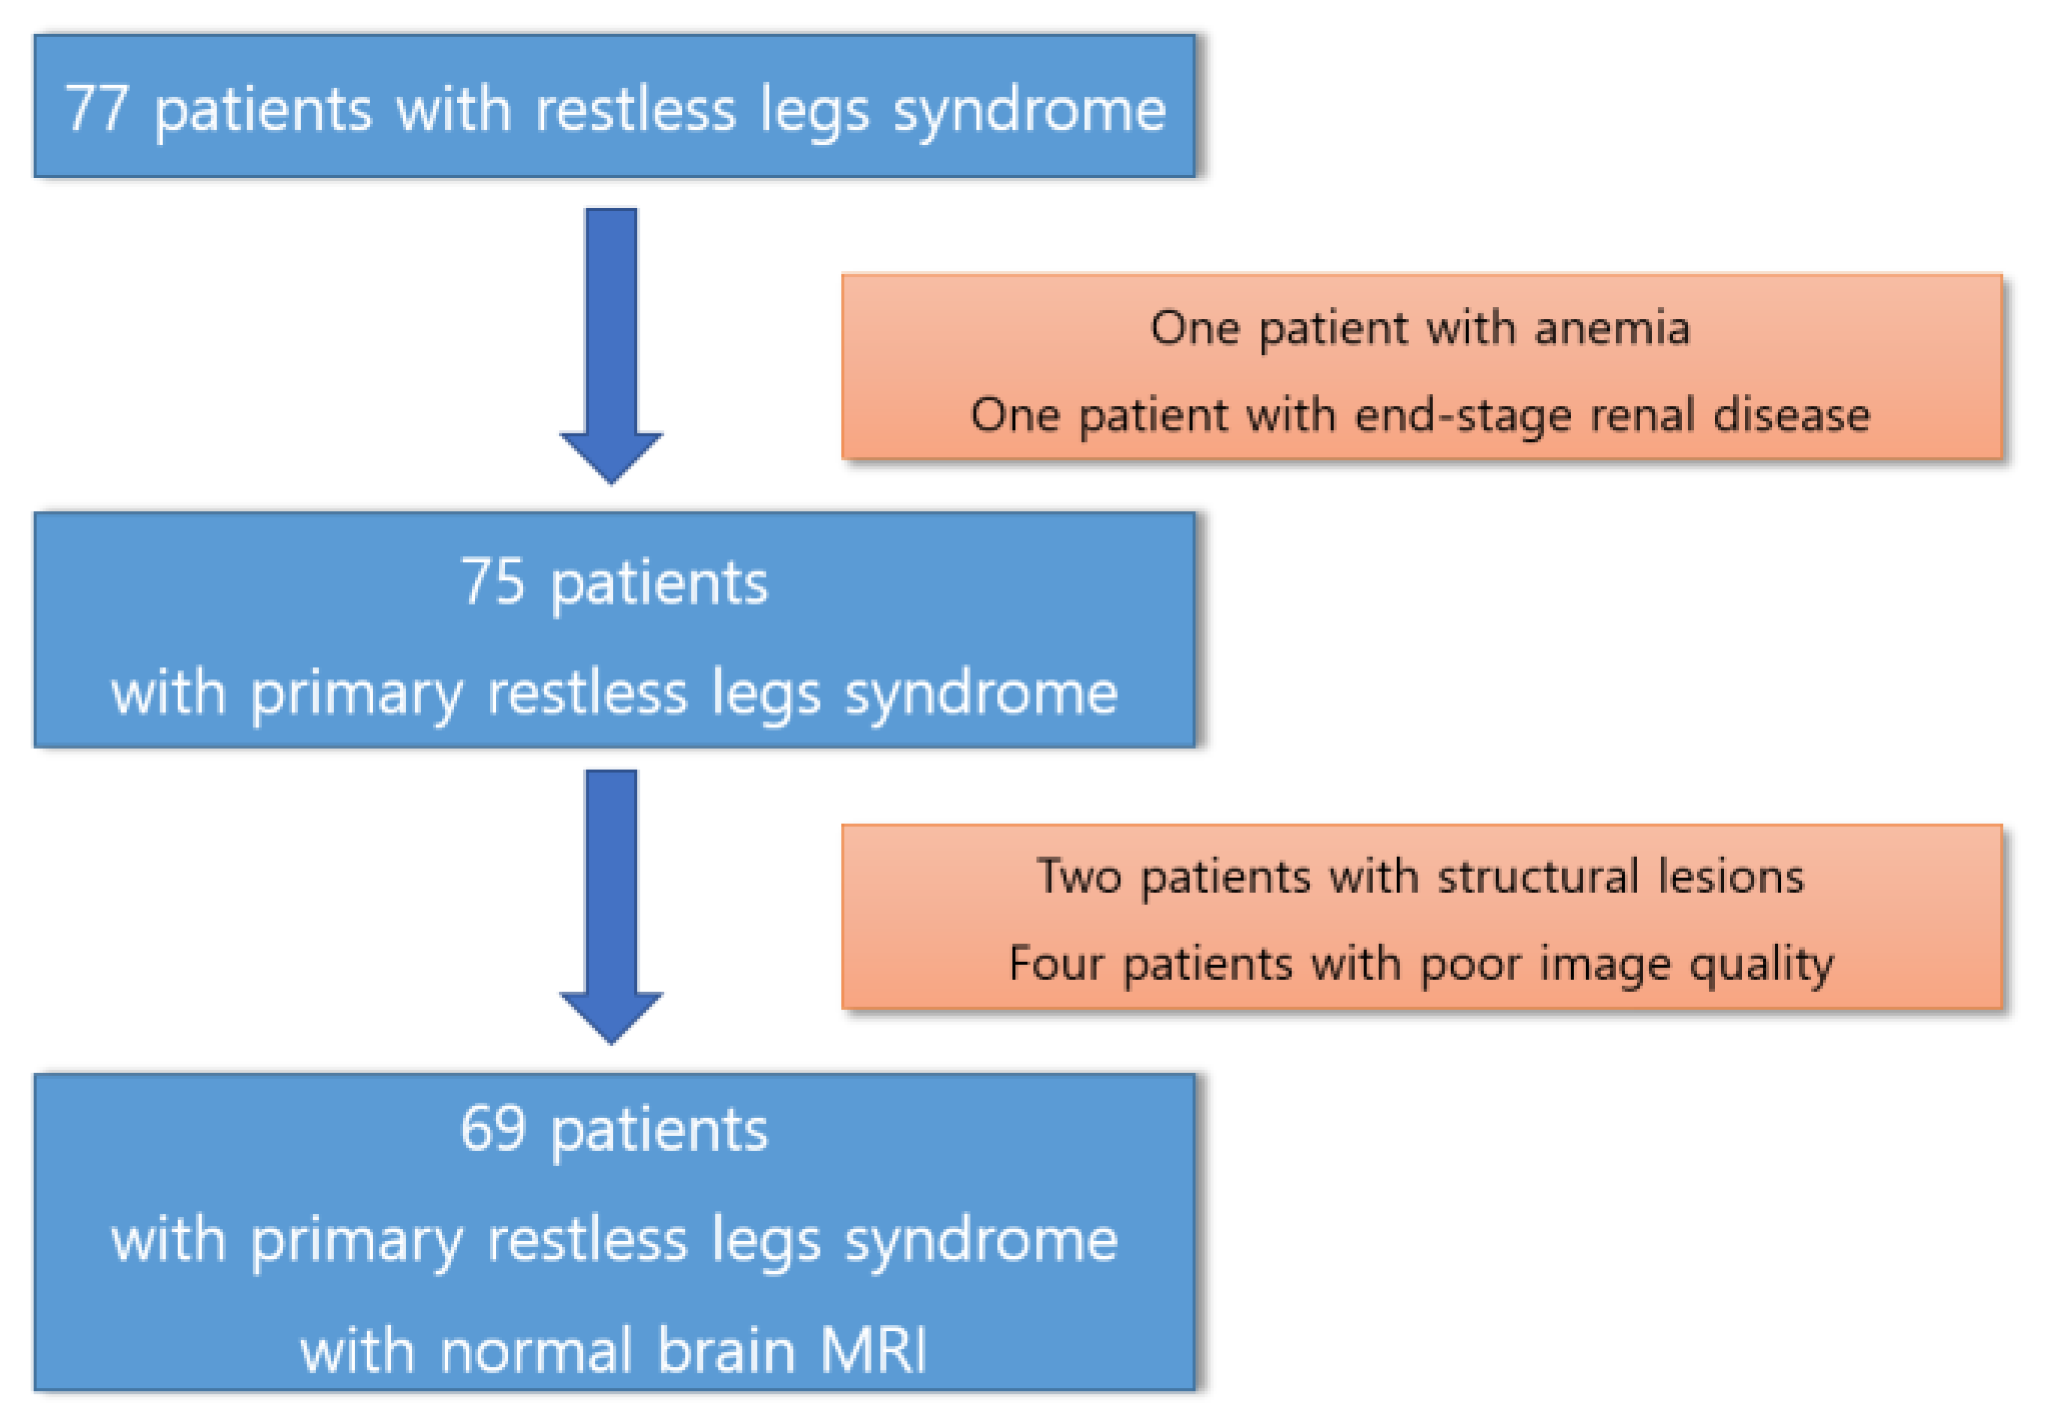

2.1. Participants

3.1. Participants